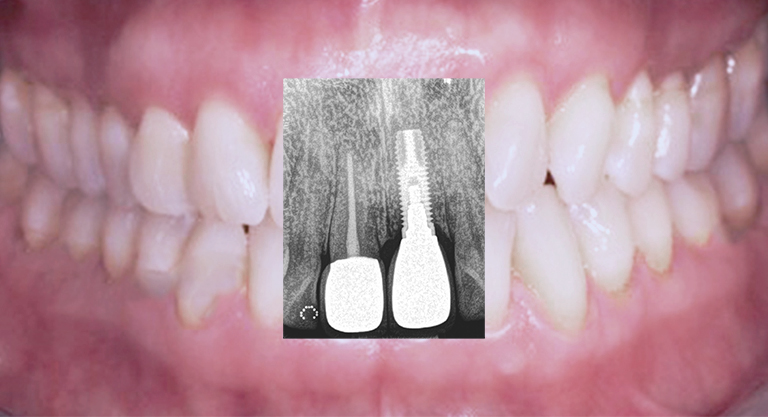

Implantat-Insertionen in Lokalanästhesie/ Narkose

Knochen- und Weichgewebsaufbau